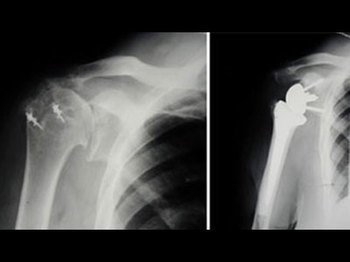

In a shoulder replacement surgery, the ball and socket joint is resurfaced and replaced with implants in severely worn out painful joint or a badly fractured non-constructible joint.